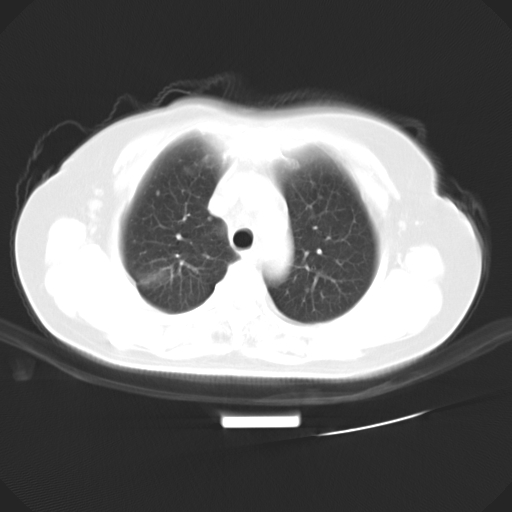

以下是引用zjzjr在2007-3-23 13:28:00的发言:[br]右肺上叶后段可见一结节状高密度影,可见毛刺征,胸膜凹陷征及血管导入征,纵隔内可见肿大淋巴结影.考虑右肺上叶周围型肺癌伴纵隔淋巴结转移.

以下是引用zjzjr在2007-3-23 13:28:00的发言:[br]右肺上叶后段可见一结节状高密度影,可见毛刺征,胸膜凹陷征及血管导入征,气管前腔静脉后可见肿大淋巴结影.考虑右肺上叶周围型肺癌伴纵隔淋巴结转移.